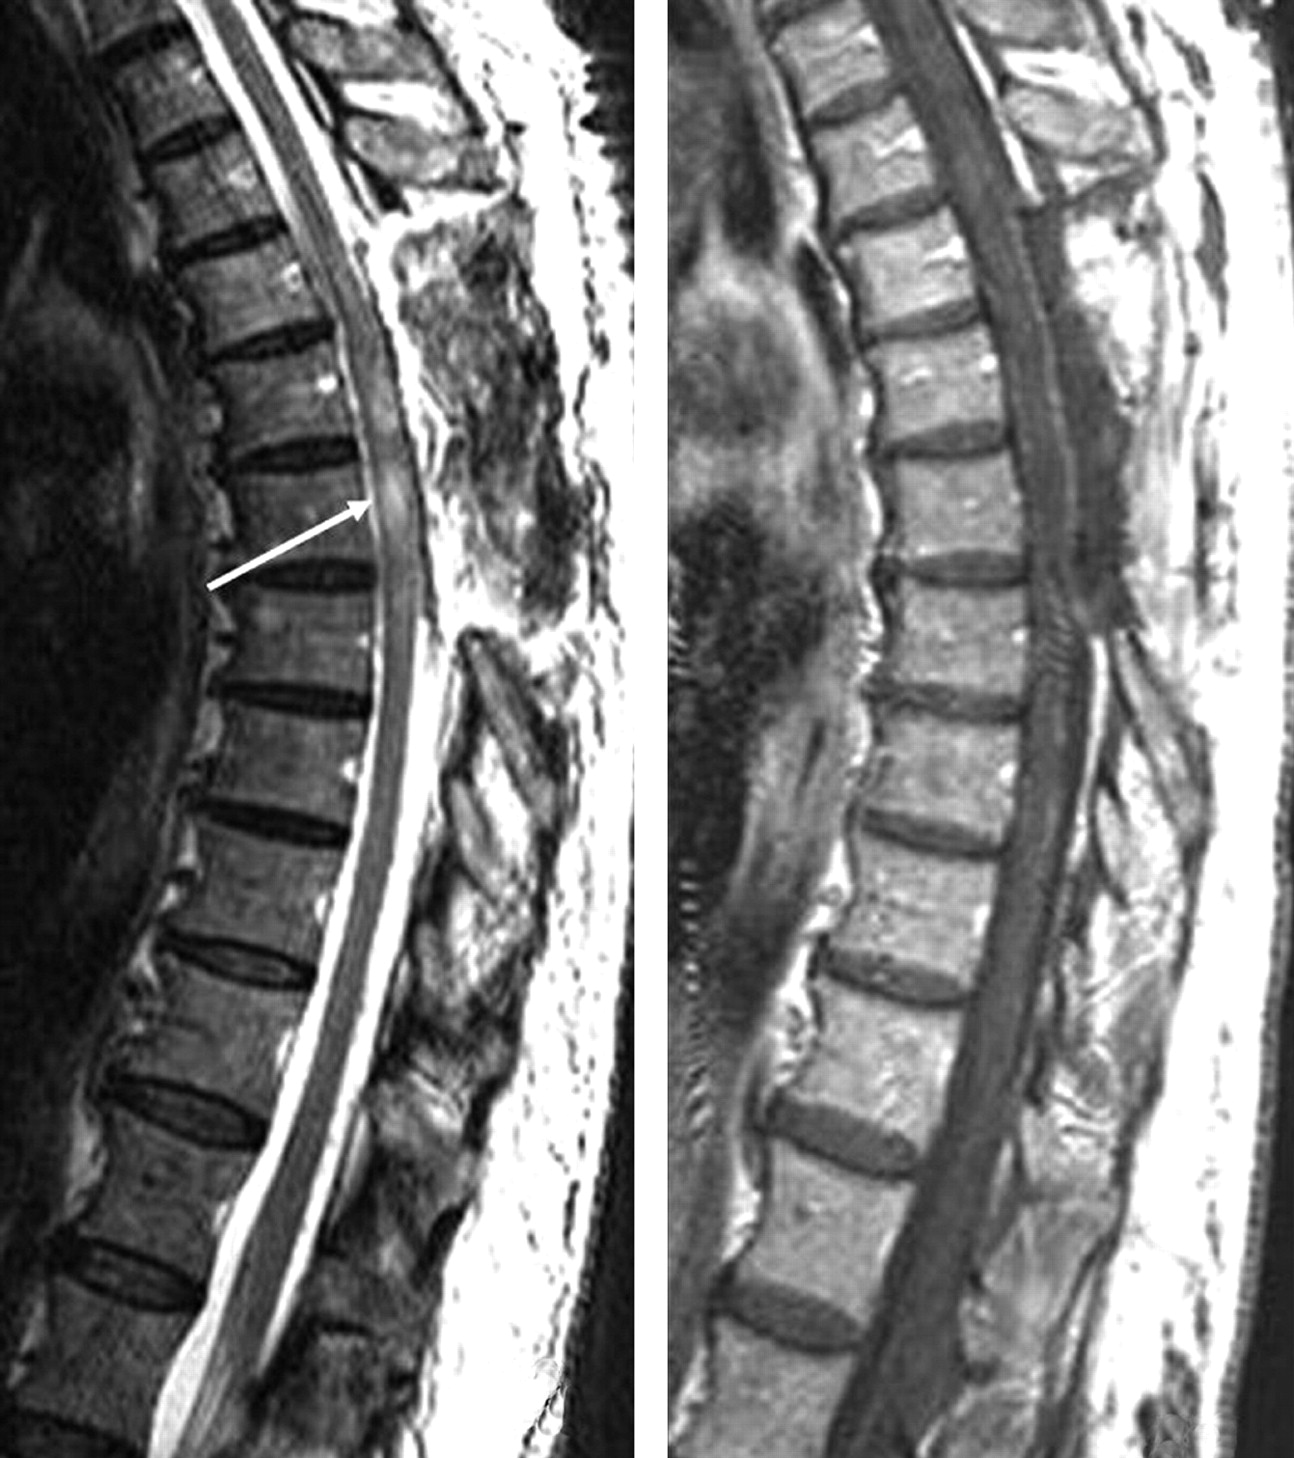

The images (Fig 1) demonstrated an extramedullary lesion, posteriorly located and extending from T5–T6 to T8, compressing the spinal cord anteriorly. The axial images (Fig 2) were the most useful in demonstrating the extramedullary location. The lesion was well defined, with some septa inside. It was essentially isointense with the CSF on all pulse sequences. The adjacent spinal cord was abnormal on T2-weighted sequences with a hyperintense appearance (T5–T6) (Fig 1A,-B). After gadolinium injection (Fig 1C,-D), there was no enhancement of the cystic extramedullary lesion. No enhancement was seen within the spinal cord, but the cord surface was covered by a rich vascular, enhancing network, probably because of the compression of the venous plexus system. No other abnormalities were found within the brain or in the spinal cord. The final preoperative diagnosis was arachnoid cyst with spinal cord compression.

Preoperative MR imaging. Sagittal T2- (A and B) and T1-weighted images before (C) and after (D) gadolinium injection. It is extremely difficult to determine whether this lesion is intra- or extramedullary. No contrast enhancement is seen. Septa are observed within the lesion.